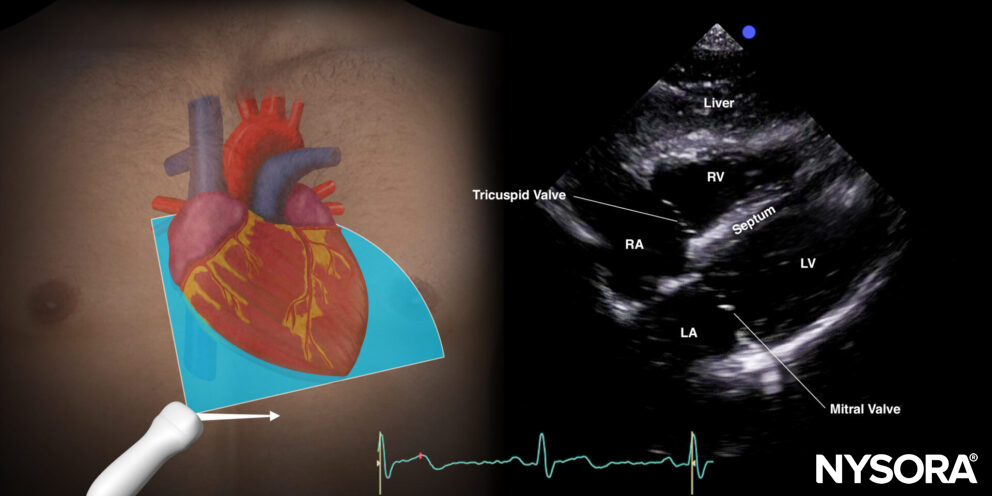

Subcostal (subxiphoid) four-chamber view (S4C)

Positioning:

Place the transducer with an overhand grip at the subcostal position with the transducer almost parallel to the skin and the index marker toward the patient’s left.

Transducer position for the subcostal four-chamber view.

Sonoanatomy:

The subcostal four-chamber view cuts the heart through the coronal plane.

Sonoanatomy of the heart in the subcostal four-chamber view. Left atrium (LA), left ventricle (LV), right atrium (RA), right ventricle (RV), septum, tricuspid valve, mitral valve.

Practical use:

- Right ventricle/left ventricle size

- Right ventricle/left ventricle function

- Pericardial effusion

- Cardiac arrest: Accessible/reliable window!